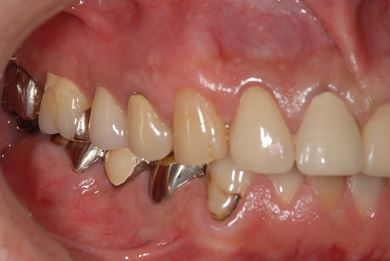

治療前

• 治療前